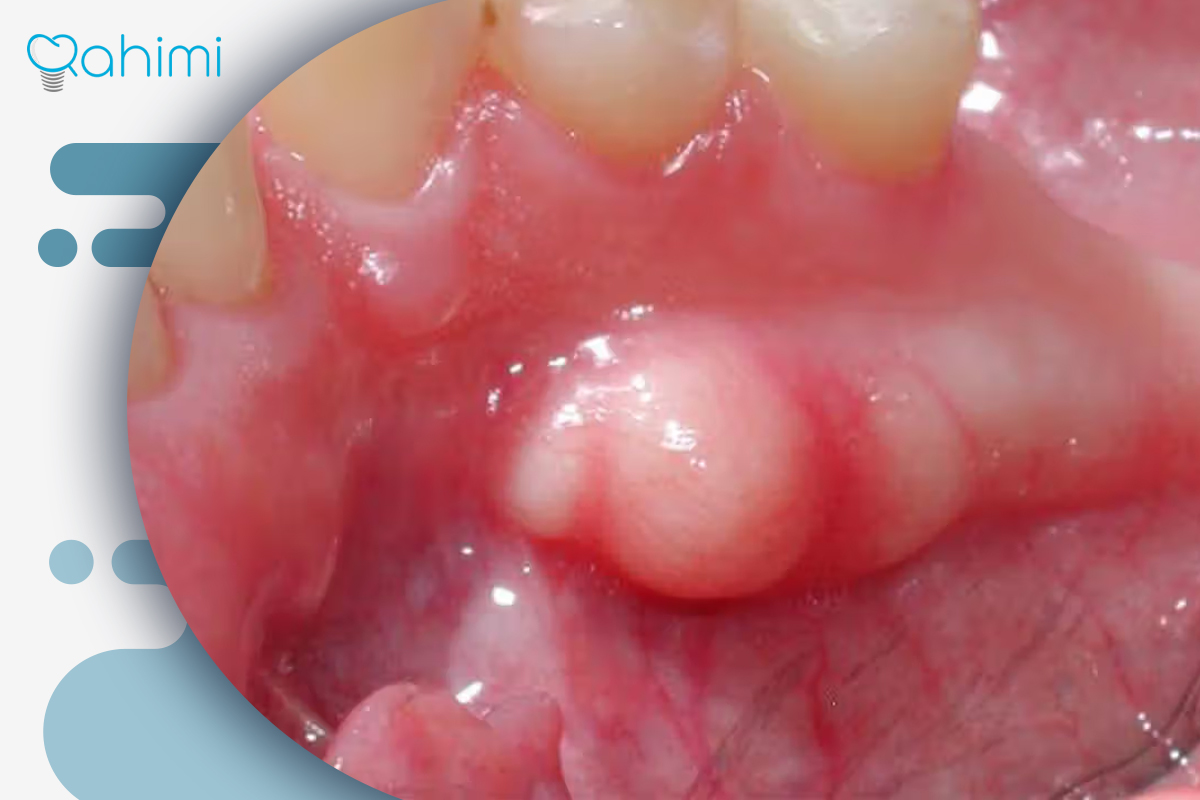

آبسه لثه: آبسه لثه یکی از شایعترین انواع جوش سفید روی لثه است که در اثر نفوذ باکتریها به فضای بین دندان و لثه ایجاد میشود. این نوع عفونت معمولاً بهصورت برآمدگی سفید پر از چرک ظاهر میشود و با درد، التهاب و گاهی بوی بد دهان همراه است. در صورت عدم درمان، چرک میتواند به بافتهای اطراف گسترش یافته و به تحلیل لثه یا حتی از بین رفتن استخوان فک منجر شود. دکتر رحیمی با بهرهگیری از روشهای جراحی دقیق و درمانهای ضدباکتریایی پیشرفته، آبسه را تخلیه و محیط دهان را به حالت سالم بازمیگرداند.

آبسه پریاپیکال (Periapical Abscess): این نوع آبسه در عمق ریشه دندان و معمولاً در اثر پوسیدگی شدید یا عفونت پالپ دندان ایجاد میشود. چرک در انتهای ریشه جمع شده و گاهی باعث ایجاد جوش سفید روی لثه در نزدیکی دندان آسیبدیده میشود. علائم آن شامل درد ضرباندار، حساسیت شدید به فشار و تب خفیف است. در دندانپزشکی دکتر رحیمی، تشخیص دقیق با رادیوگرافی دیجیتال انجام میشود و در صورت لزوم، درمان ریشه (عصبکشی) یا جراحی لثه برای تخلیه عفونت صورت میگیرد.